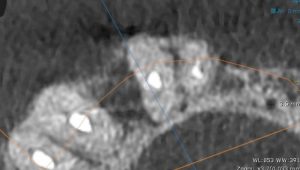

【CT画像でも遠心側に病巣】

【根尖には透過像がない】

【明らかに遠心側に透過像がある】